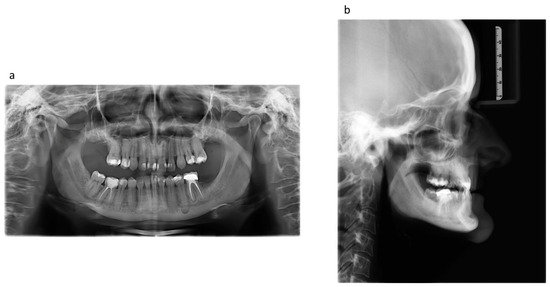

2. Case Report